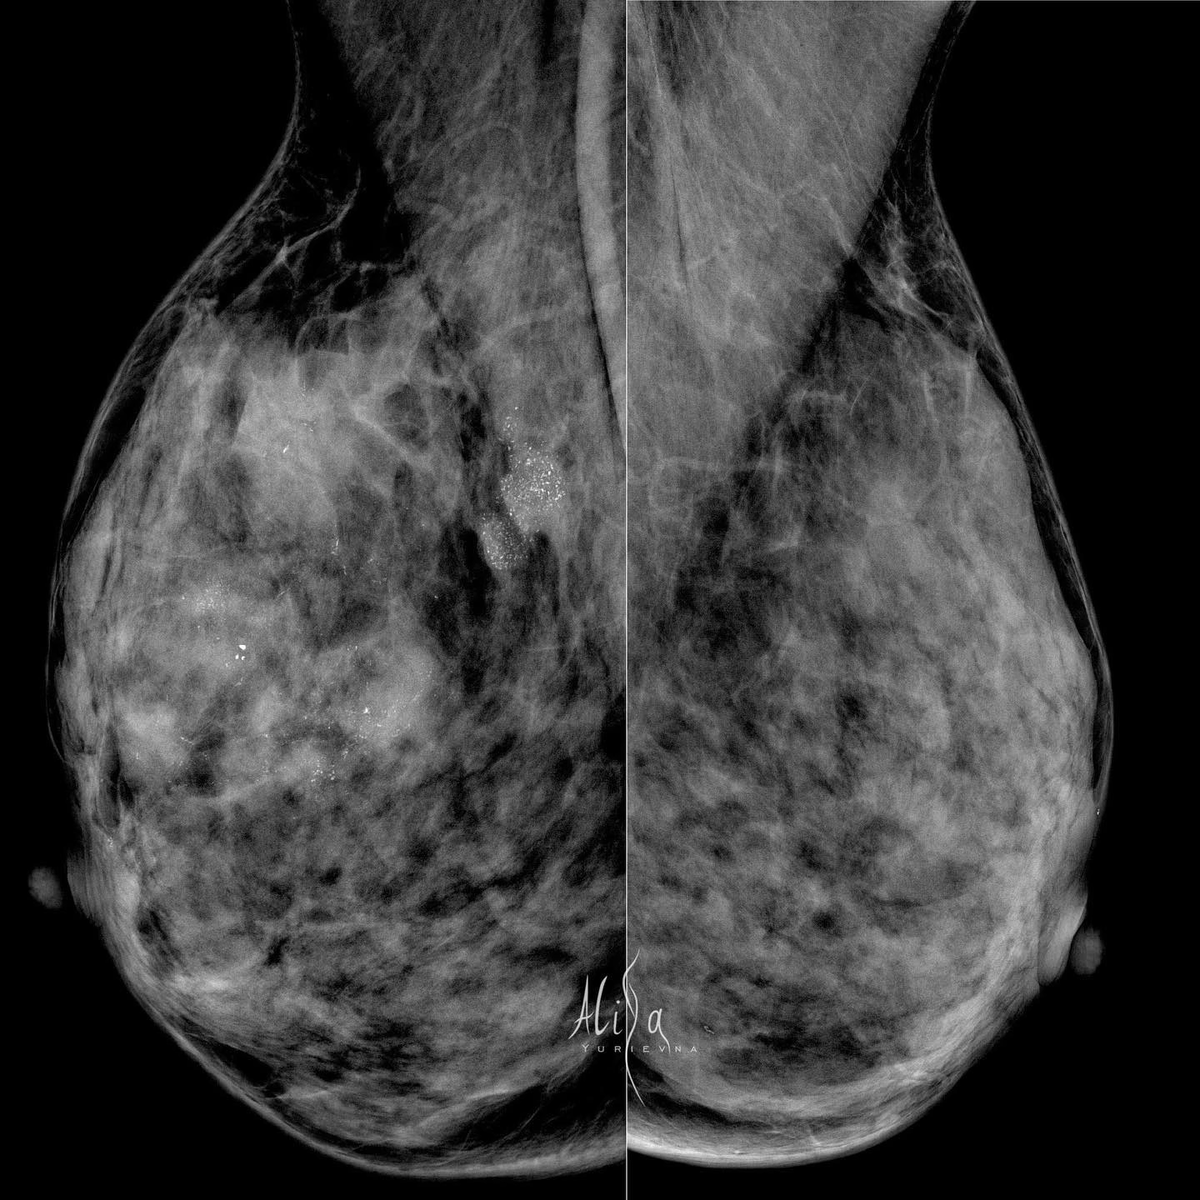

Женщина 38 лет

Инвазивная карцинома молочной железы, неспецифицированная, G2. ER 8 баллов, PR 4 балла, HER2/neu 1+, Ki67 ~ 30%

P.S: с точки зрения рентгенологии тут, конечно, глаз радуется от разнообразия проявлений